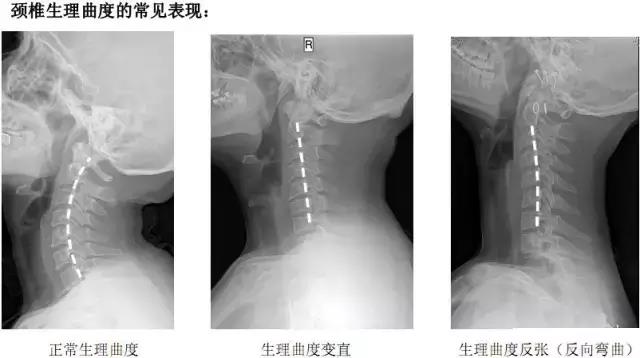

第一,颈项部的不适,主要是由于颈椎生理曲度变直引起的。并且没有较为严重的颈椎生理结构改变。正常情况下,颈椎有一个前凸的弧度,被称为生理性前凸。人们在清醒的情况下,无论是工作还是学习,无论站立、走路还是坐位姿势,都以保持这种自然姿势为最舒服。长时间过度低头,颈后部会感到疲劳。

颈椎生理曲度变直、反弓

颈椎生理曲度的几种表现